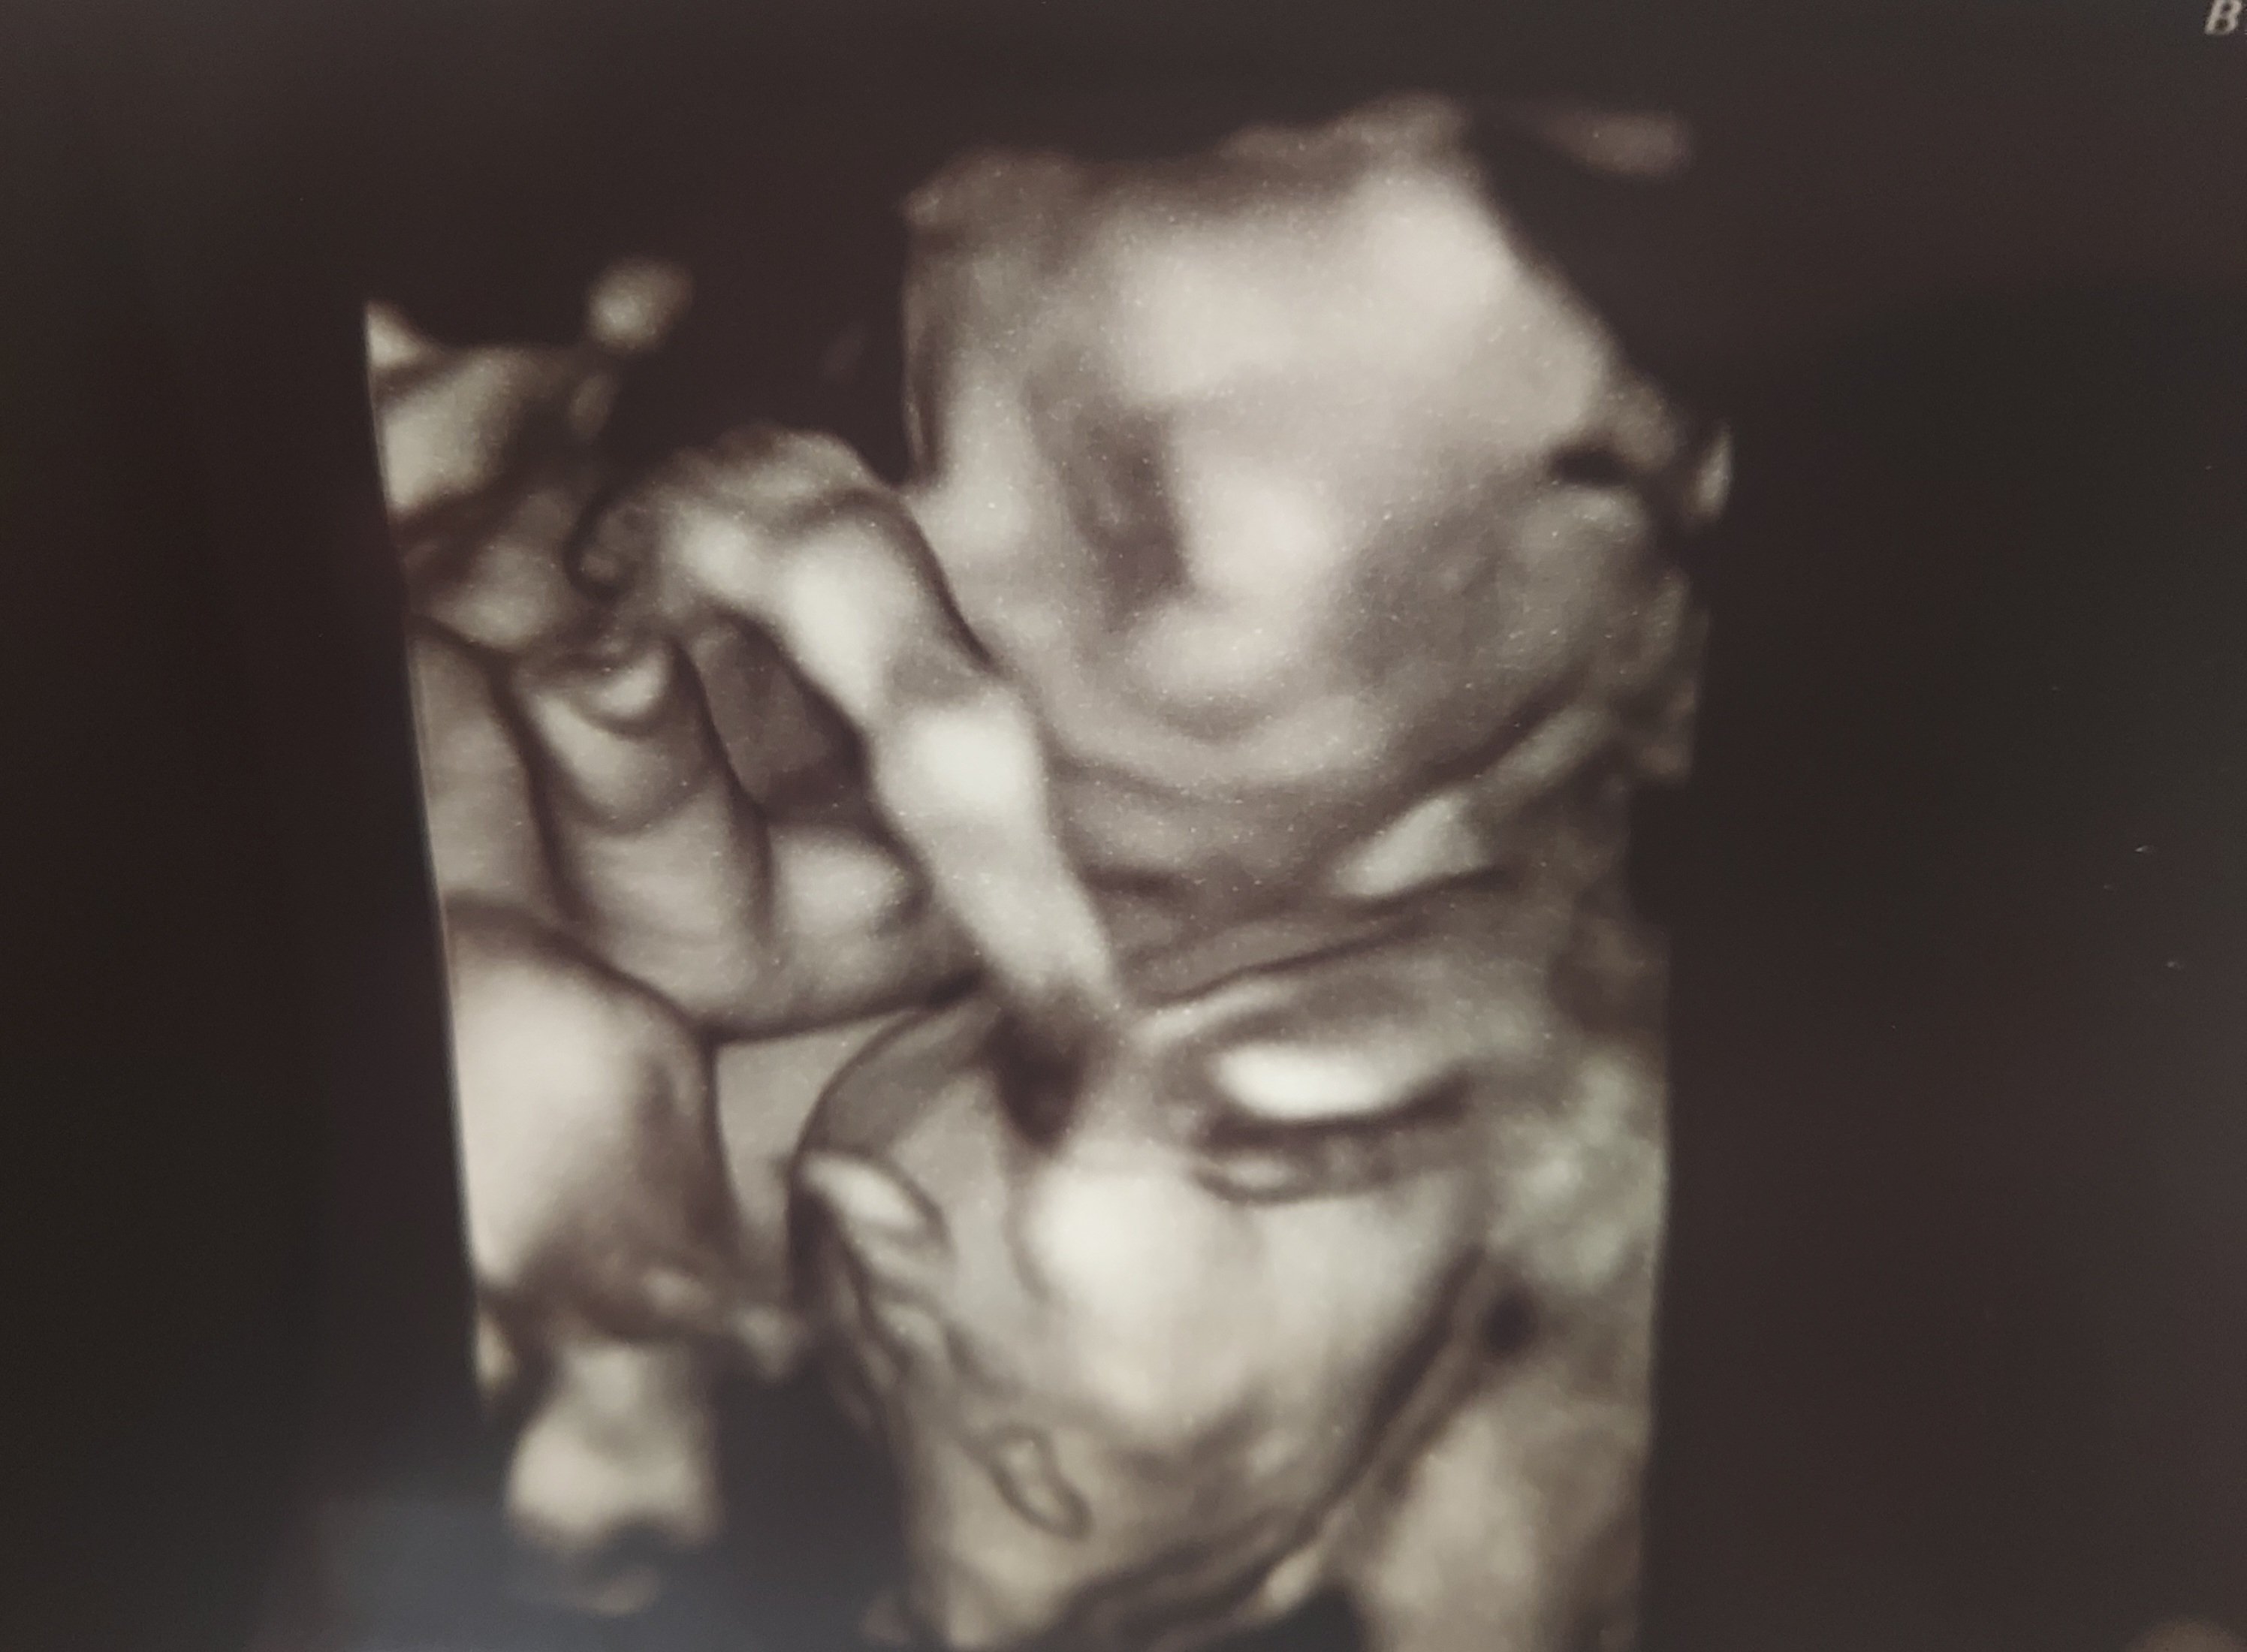

Nugget at 23+4. We didn’t get 3D with my first so this is awesome!